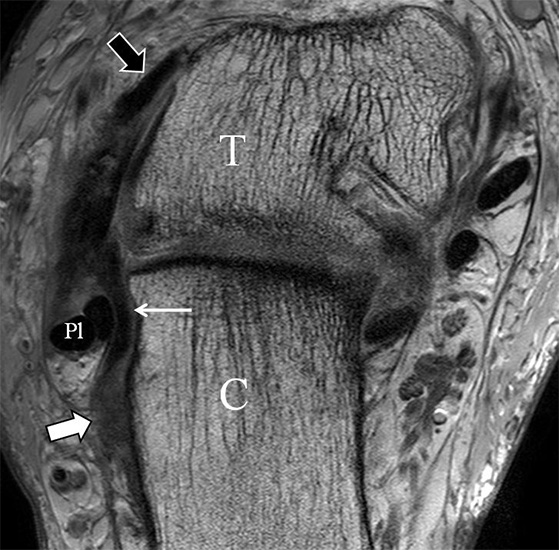

Der Ursprung des Ligamentum fibulocalcaneare liegt unmittelbar kaudal und dorsal des Ursprungs des Ligamentum fibulotalare anterius, so dass gehäuft kombinierte Verletzungen und auch ein gemeinsamer knöcherner Ausriss beobachtet werden. Nach kaudal dorsal verläuft das Band dann nach medial konvex unter die Peroneussehnen. Danach ist ein schräg deszendierender, gestreckter Verlauf bis zum calcanearen Ansatz abgrenzbar (Abb. 10). Dieser zu allen drei Standardebenen schräge Verlauf erschwert häufig die Diagnostik des LFC vor allem bei subtileren Verletzungen. Spezialprojektionen, die dem Bandverlauf orthograd folgen (entweder schräg coronar oder schräg sagittal) erleichtern auch hier die Diagnostik (Abb. 11) insbesondere nicht dislozierter Avulsionen. Assoziierte Verletzungen der Peroneussehnenloge müssen mit beurteilt werden, wobei neben Verletzungen der Sehnen und Sehnenscheiden die Beurteilung des Retinaculum peroneum superius und inferius wichtig ist. In einem Kollektiv von Patienten mit chronischen Außenbandinstabilitäten weisen 50% der Patienten eine Verletzung dieser Strukturen auf 5. Auch hier erleichtern hochauflösende Techniken die Diagnostik (Abb. 12).